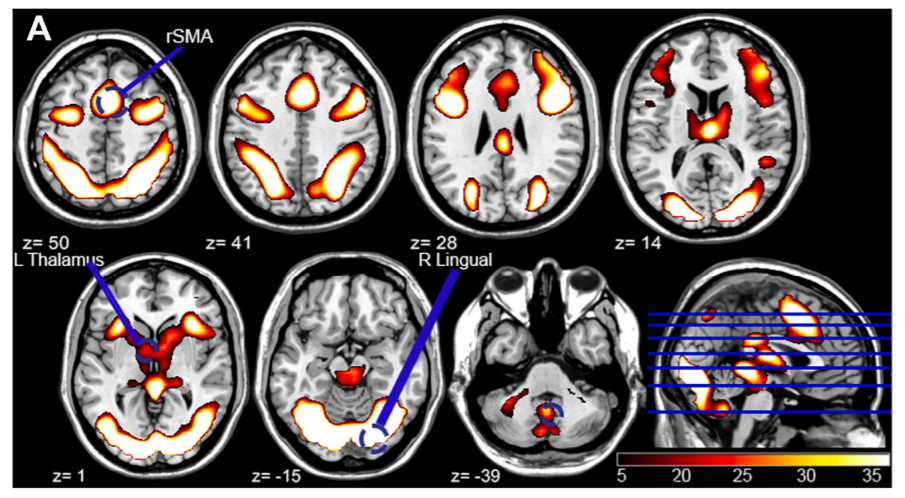

▲玩电子游戏可以影响特定脑区的活动水平(图片来源:参考资料[2])

成像结果显示,这种快速的反应与特定脑区活动增强有关,包括右侧辅助运动区、左侧丘脑。这些脑区的活动越强,志愿者的表现往往会更好。